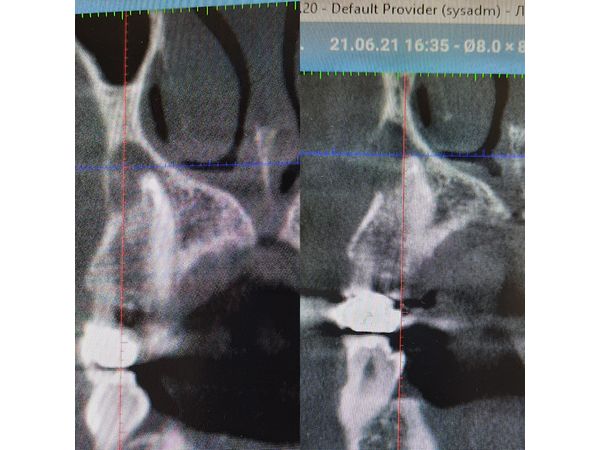

Через 3 месяца после лечения ей повторно провели КТ, которая показала, что объём разрушения костной ткани уменьшился, а кортикальная пластинка начала восстанавливаться. Девушке поставили коронку из диоксида циркония.

Через полгода пациентка пришла на контрольный осмотр. Судя по КТ, очаг разрушения уменьшился на 80 %. Боль в зубе не появлялась.